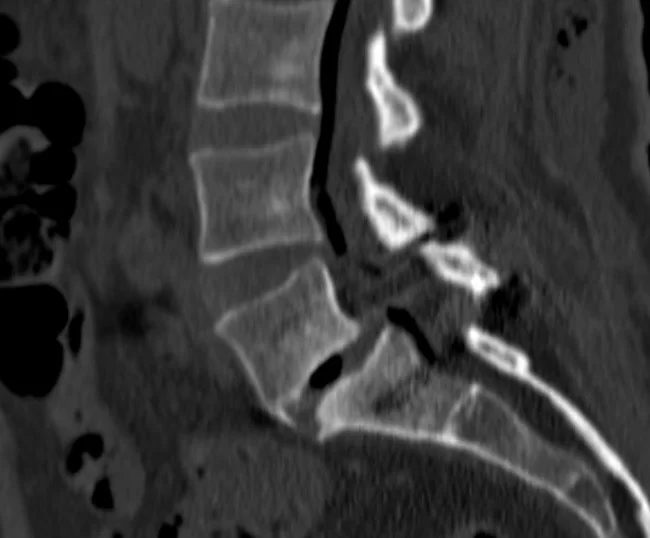

Σημαντική βοήθεια για τη διενέργεια τέτοιων επεμβάσεων αποτελεί η τρισδιάστατη νευροπλοήγηση της σπονδυλικής στήλης, η οποία επιτρέπει τα υλικά να τοποθετούνται με ακρίβεια χιλιοστού (Εικόνα 1 και 2).